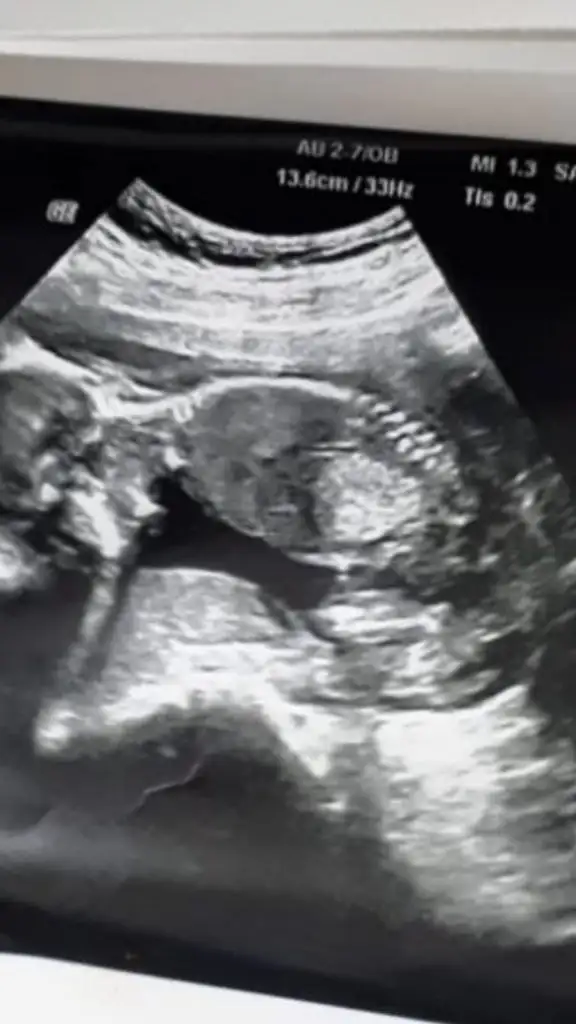

Bu da pazartesi 14+2 de gittim bunu atmadum ama amuda kalkmis resmen Sipa 😅doktor bu sefer ben sormadan tekrar erkek dedi

20200921_114838.webp bunda bacaklarini gostermiyordu ama sadece govde ve kafa . Kafasini asagiya sıkıştırms yaramaz 😄

Eki Görüntüle 2695937 bunda bacaklarini gostermiyordu ama sadece govde ve kafa . Kafasini asagiya sıkıştırms yaramaz 😄

Evet erkek pipi oracıkta 🙈 sağlıkla kucağına alırsın inşallah canım 🤗